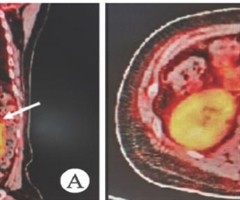

抗血栓和辜丸减张挽救长时间大角度辜丸扭转2例报告

辜丸扭转是急症,扭转时间超过 6h 且扭转角度大的病例经术中复位、温敷等措施后,若睾丸血供未恢复,须切除睾丸。国内尚未检索到通过肝素精索注射联合睾丸切开减张挽救扭转辜丸的报道。收治2例患者,辜丸长时间扭转且扭转角度达 720∘ ,采用此法成...